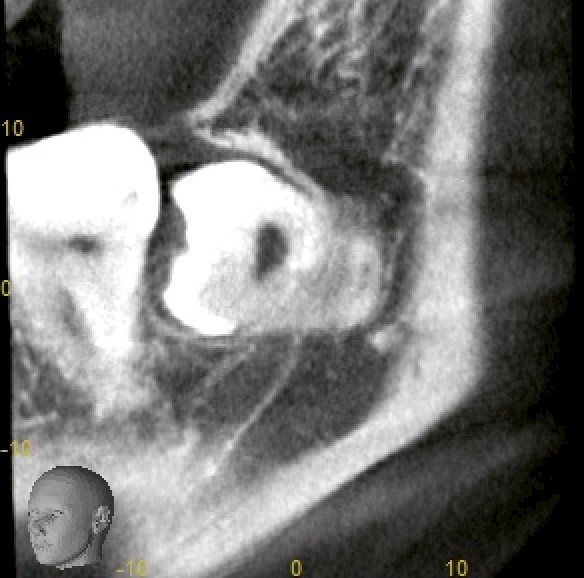

CTにて確認したところ、

・下顎:深い完全埋伏

・歯根は明らかに湾曲

・下歯槽神経に近接〜一部接触所見

・上顎:完全埋伏

・上顎洞に極めて近接

という状況でした。

いずれも「難易度が低い」とは言えないケースです。